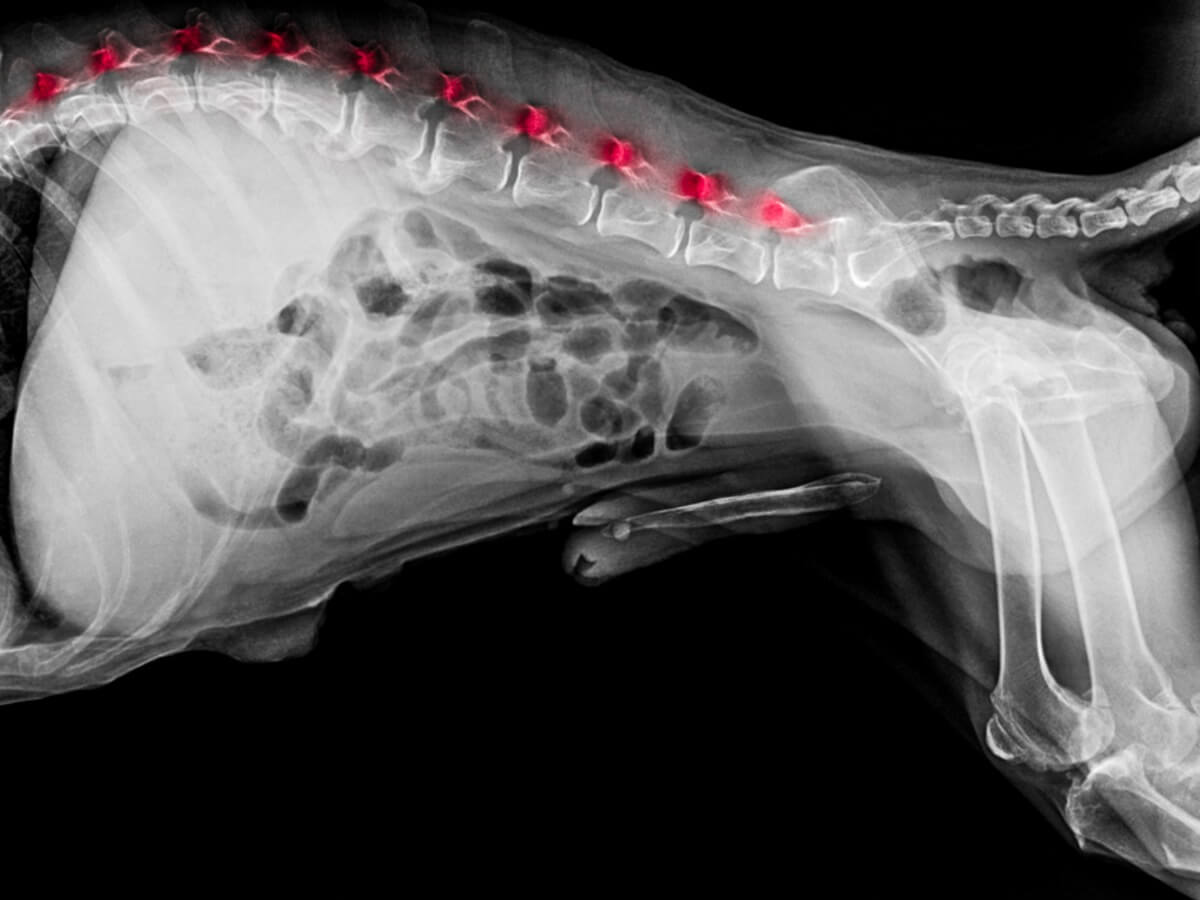

Como primera prueba, el veterinario revisará los reflejos y comportamientos del perro frente a diversos estímulos. Si detecta una señal de alarma, es probable que pida un análisis visual por medio de rayos X o resonancia magnética. Además, para tener un panorama más completo, se puede pedir un perfil sanguíneo.